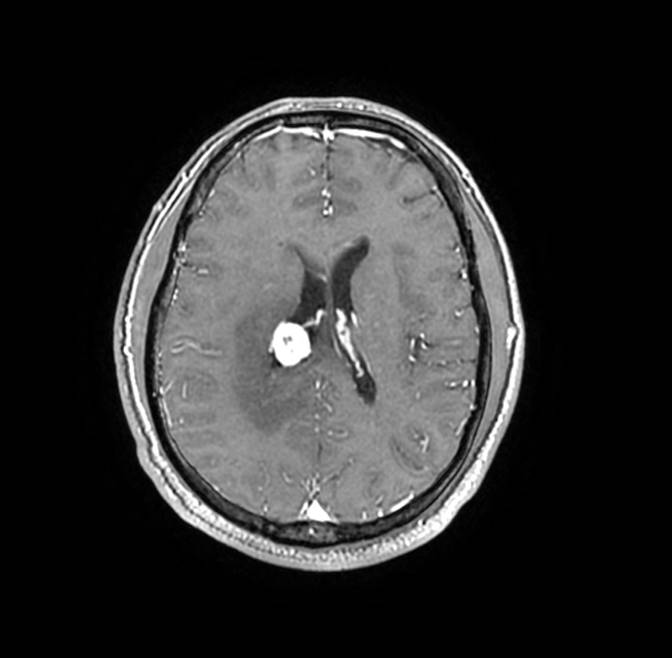

磁共振影像圖

圖4

MR診斷:右側(cè)側(cè)腦室三角區(qū)及側(cè)腦室旁占位,考慮惡性腫瘤可能,間變型腦膜瘤?轉(zhuǎn)移瘤?

MR鑒別診斷

常規(guī)MR檢查是診斷腦膜瘤的有效手段,可以明確腫瘤發(fā)生的部位、形態(tài)和數(shù)目等特征以及病變向鄰近腦實質(zhì)侵犯的程度和范圍,典型腦膜瘤呈等或(和)稍長T1、等或(和)稍長T2信號,??娠@示完整的包膜,增強掃描因腫瘤內(nèi)部新生血管通透性不同呈不同程度強化,由于腫瘤組織的強化程度與腫瘤的惡性程度不完全一致,導致MR常規(guī)檢查在腦膜瘤分級分型方面仍存在一定的困難。擴散加權成像( diffusion weighted imaging,DWI) 及表觀擴散系數(shù)( apparent diffusion coefficient,ADC) 被廣泛用于腦腫瘤的分級、分子分型和腫瘤侵襲性預測,并取得了良好的性能。目前,對于非典型腦膜瘤腦實質(zhì)侵犯的診斷的金標準依賴于組織病理學。